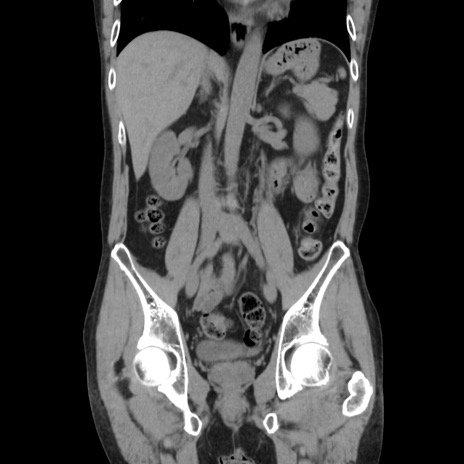

症例37(冠状断像)

【症例】40歳代 男性

【主訴】腹痛

【現病歴】4時間ほど前に電車に乗車中に臍部上より腹痛出現。徐々に増悪し起立困難となり、救急外来受診。生ものは数日食べていない。今朝お雑煮を食べた。

【身体所見】BT 36.8℃、BP 117/84mmHg、HR 91/min、SpO2 97%、苦悶様、腹部:臍上部広範囲圧痛あり、反跳痛±

【データ】WBC 8100、CRP 0.03